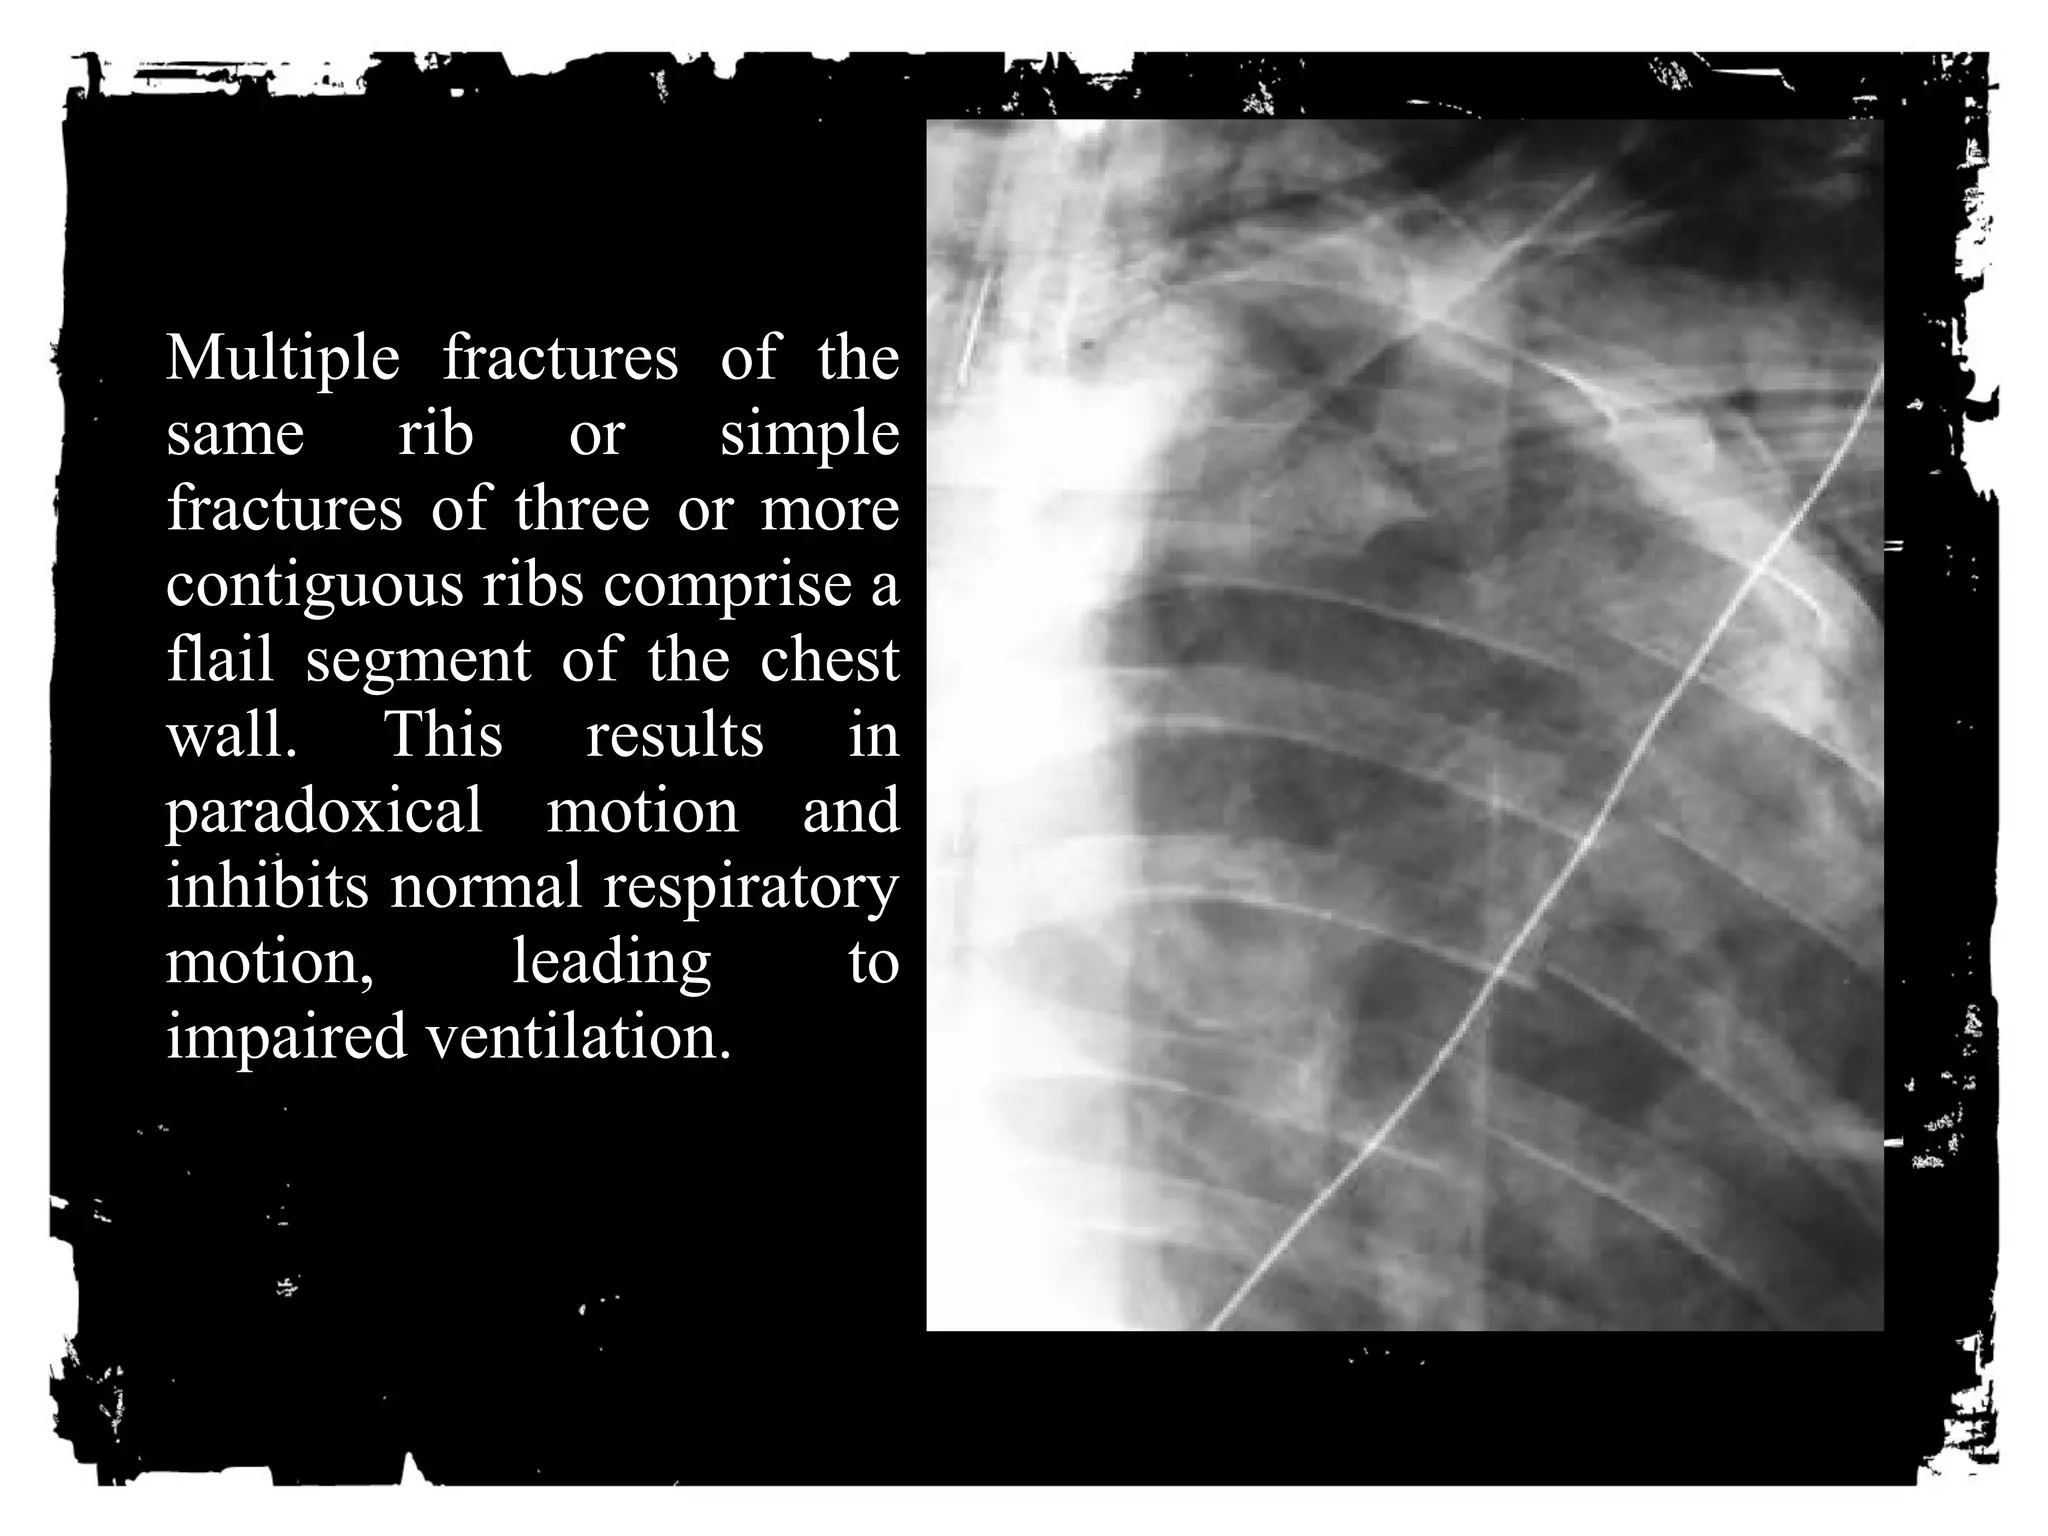

Multiple fractures of the

same rib or simple

fractures of three or more

contiguous ribs comprise a

flail segment of the chest

wall. This results in

paradoxical motion and

inhibits normal respiratory

motion, leading to

impaired ventilation.

Simple rib fractures are

frequently encountered on chest

radiographs and rarely require

further studies. However,

complication of rib fractures such

as pneumothorax, hemothorax,

lung contusions, and lacerations

are of more important clinical

impact than the fracture itself